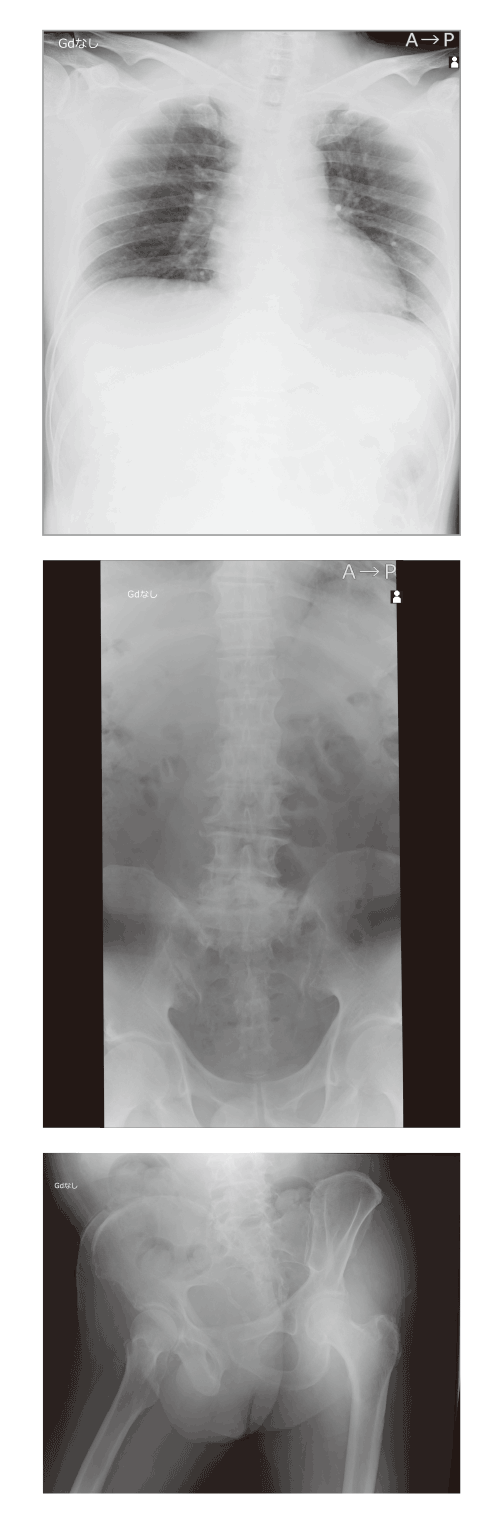

REALISM処理

Hybrid処理(従来処理)

画像全体の描出とコントラスト維持の両立

改良されたダイナミックレンジ圧縮の処理と、新規のLUT(階調カーブ)により、低線量域から高線量域まで各構造物を分離良く表現し、白トビ・黒ツブレを起こすことなく画像全体を自然なままに描出することで立体感のある画像を提供します。

高解像度空間への拡張

AeroDR fineの特徴である100μmを最大限に活かし、周波数強調処理の改良により、高周波領域を忠実に描出可能に。

高解像ならではの微細構造の表現を実現します。